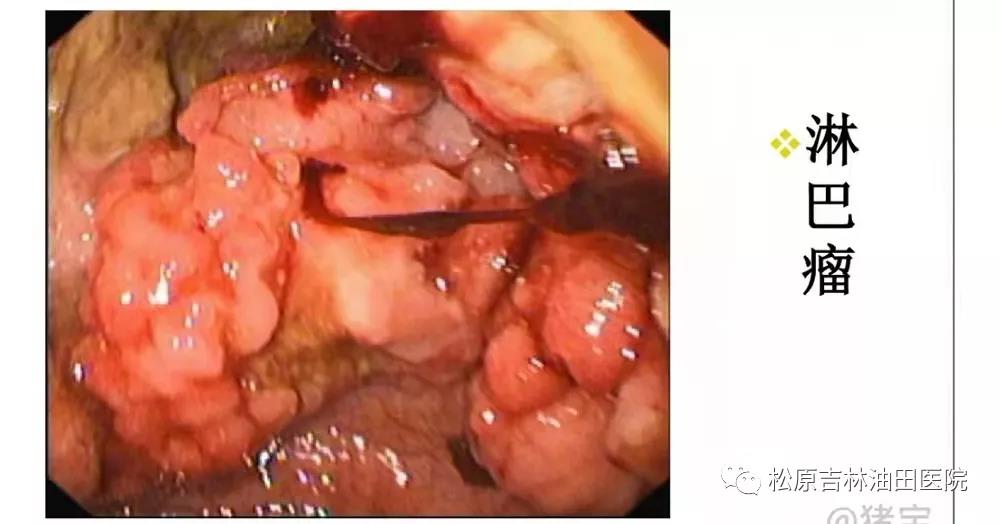

(3)胃癌及胃黏膜相关性淋巴样组织样恶性淋巴瘤

幽门螺杆菌的代谢产物直接毒害黏膜引起炎症反应,其本身也具有基因毒性作用,从而引发胃黏膜的恶性转化,引发胃癌。